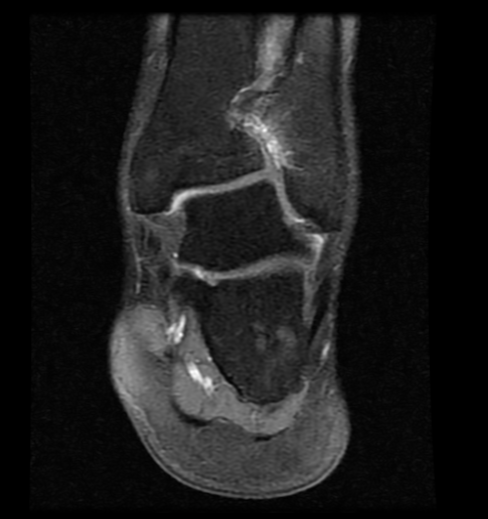

Arthritic flatfoot

Pre-op MRI